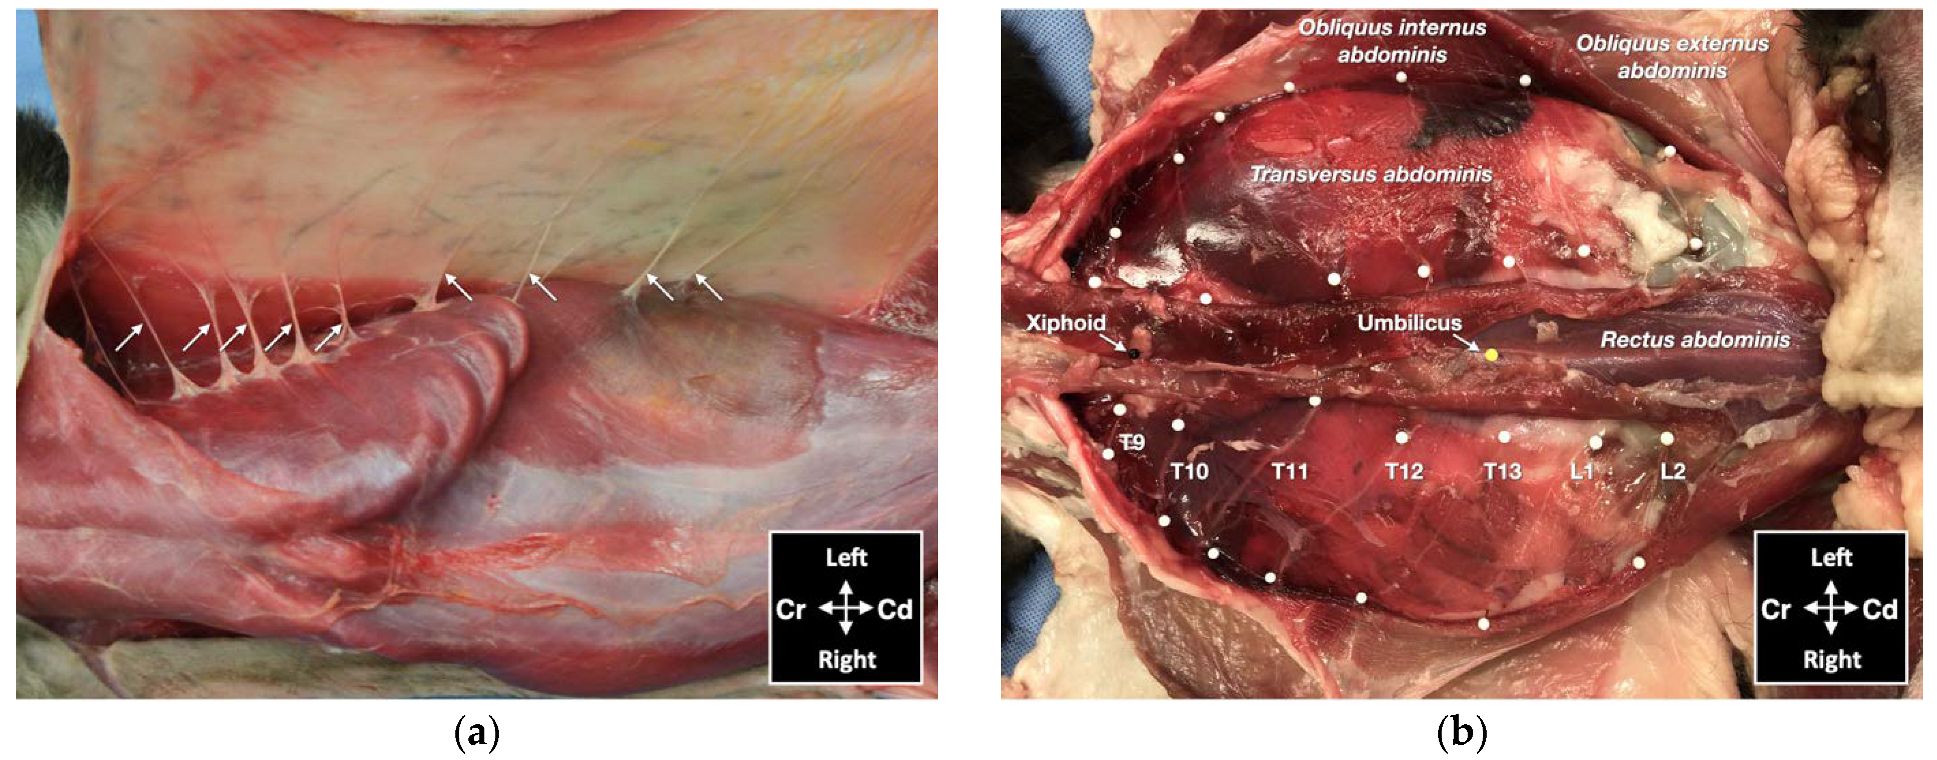

For the lateral TAP injection, the transducer was positioned parallel to the long axis of the cat (longitudinal plane), at 3–4 cm lateral to the abdominal midline and about 1 cm lateral to the mammary line, immediately caudal to the last rib (Figure 2). The transducer was slide laterally until the belly of the m. obliquus internus abdominis could be identified between the mm. obliquus externus and transversus abdominis. The needle was introduced in-plane in a ventrocranial-to-dorsocaudal orientation and continually visualized until its tip was advanced into the TAP between the m. obliquus internus abdominis and the m. transversus abdominis (Figure 2). Then, the assigned injectate volume was administered (0.5 mL/kg in TAP-L versus 0.25 mL/kg in TAP-SL).

Figure 2. Ultrasound transducer position, needle puncture site, sonographic image, and schematic representation of the lateral TAP injection in a cat cadaver; Cd, caudal; Cr, cranial, L, lateral; Lt, left; M, medial; Rt, right. Adapted from: Garbin, M.; Benito, J.; Ruel, H.L.M.; Watanabe, R.; Monteiro, B.P.; Cagnardi, P.; Steagall, P.V. Pharmacokinetics of bupivacaine following administration by an ultrasound-guided transversus abdominis plane block in cats undergoing ovariohysterectomy. Pharmaceutics 2022, 14, 1548. https://doi.org/10.3390/pharmaceutics14081548 (accessed on 1 August 2022).